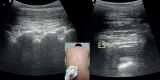

Ultrasonography has gained popularity in recent years among anaesthesiologists and being used widely for regional blocks and central venous catheterization. Ultrasonography for neuraxial blocks was found beneficial especially for determining the correct needle insertion site and estimating the needle insertion depth of epidural space. In many recent studies, ultrasound guided epidural and spinal blocks have been evaluated among obstetric patients. Pre-procedural lumbar ultrasonography and real time ultrasound guidance for neuraxial blocks was the subject of these studies. We aimed to evaluate lumbar ultrasonography for obstetric neuraxial blocks. We describe the principles of lumbar ultrasound scanning techniques and present a practical review of lumbar sonoanatomy. We discuss the potential impact and benefits of the ultrasound-guided technique in improving obstetric neuraxial blocks and limitations of its use in clinical practice, based on previous studies.